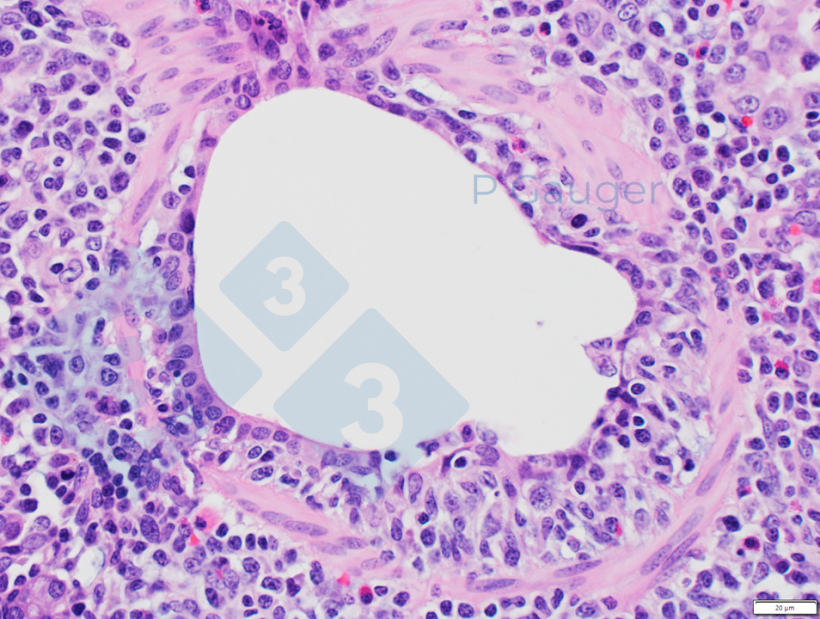

- A bronquiolite necrosante é frequentemente considerada patognomônica da infecção pelo vírus influenza A em suínos.

Figura 4: Histopatologia pulmonar mostrando adelgaçamento do epitélio bronquiolar, que é um exemplo de necrose. (Fonte da foto: Phil Gauger ISUVDL). - As lesões características aparecem alguns dias após a disseminação do vírus em suínos, especialmente quando há coinfecções.